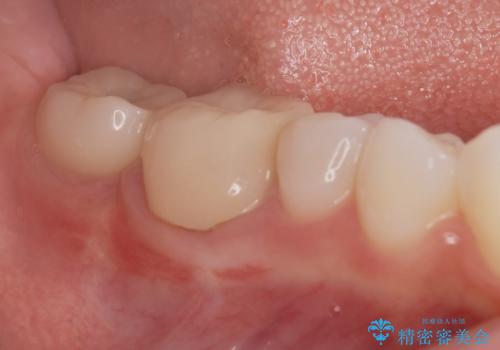

![[ インプラント体・カスタムアバットメント・ジルコニアクラウン ] インプラントの構造の症例 治療前](https://seimitsushinbi.jp/wp/wp-content/uploads/2024/02/d7b3d7509c0cc77833268d7096e1730b-500x350.jpg?v=1708928260)

![[ インプラント体・カスタムアバットメント・ジルコニアクラウン ] インプラントの構造の症例 治療後](https://seimitsushinbi.jp/wp/wp-content/uploads/2024/02/4f5d249988cfa0d7689dd16755d46820-500x350.jpg?v=1708928265)